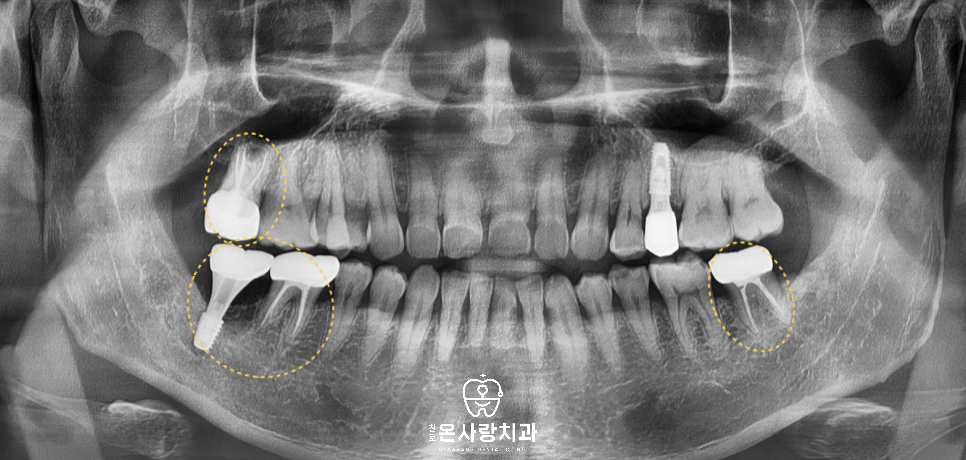

진단 후 가장 먼저 사랑니 발치를

진행하여 더 이상의 손상이

이어지지 않도록 하였습니다.

그다음 사랑니로 인해 영향을

가장 크게 받은 부위를 중심으로

앞쪽 치아 상태를 하나씩 평가하고,

예후가 좋은 치아는 살리는 방향으로

예후가 불량한 치아는 발치를 통한

수복을 계획했습니다.

오른쪽 위와 왼쪽 아래의 큰 어금니는

깊은 우식이 있어 신경치료 후

크라운 수복을 진행했습니다.

가장 큰 문제는 오른쪽

아래 큰 어금니부위였습니다.

오랜 기간 보이지 않는 쪽에서

염증이 진행되면서 치조골이

뿌리 주변에 거의 남아 있지 않았고,

저작 시 심한 통증과 흔들림이 있어

두 번째 큰어금니는

발치가 필수였습니다.

발치 후 치조골 이식을 시행해

잇몸뼈를 회복시키고

임플란트를 식립하였으며

그로 인해 영향을 받았던

첫 번째 큰어금니는 치조골이

균형적으로 회복된 이후 신경치료와

크라운을 통해 보존할 수 있었습니다.

이와 별개의 문제로 기존에

신경치료가 되어 있던

왼쪽 위의 작은어금니는

치관이 거의 남지 않은 상태였고,

구조적으로 힘을 지지할 수 없어

천호역치과을 통해서 발치를 결정한 뒤

임플란트를 계획했습니다.